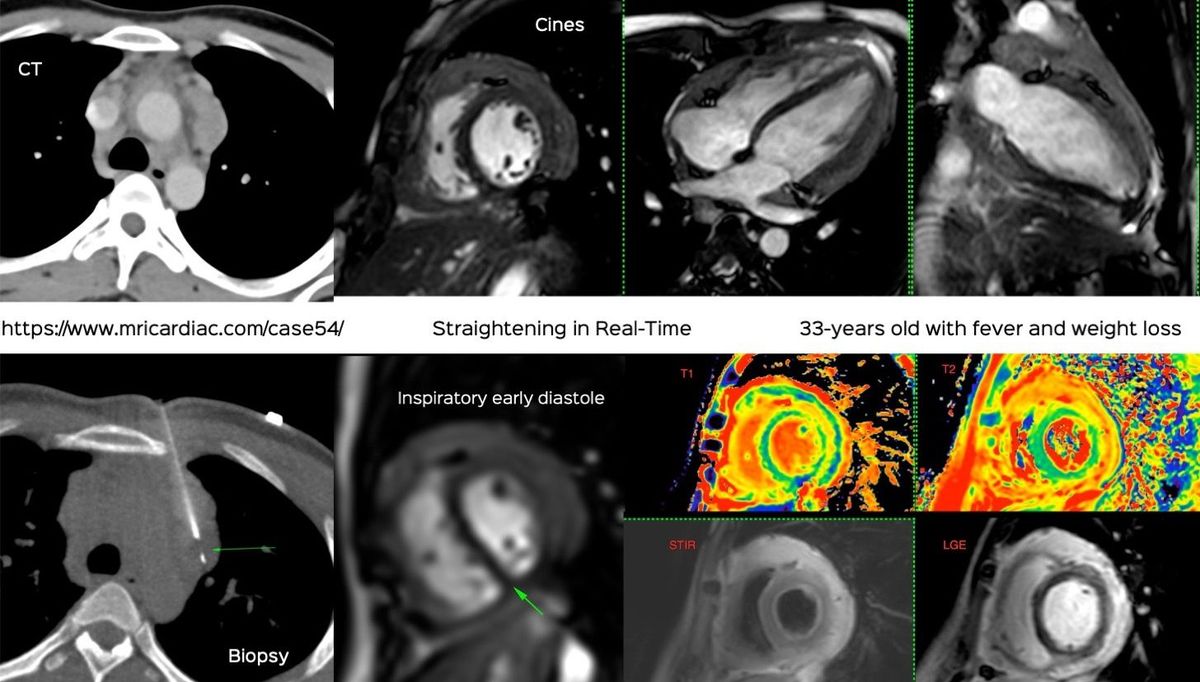

Real-time MRI in this case of tuberculous acute effusive-constrictive pericarditis

This 33-years old had fever and weight loss, mild clubbing on examination and pericardial disease on echo.

A cardiac MRI showed extensive pericardial disease with lymphadenopathy. The video discusses the case, the use of real-time MRI to make a diagnosis of constriction and how a CT guided biopsy helped with the etiological diagnosis.